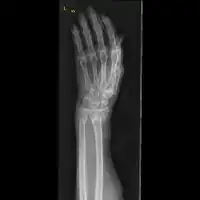

The diagnosis of a forearm fracture is made by first inspecting and then feeling the injured forearm for any obvious deformity and tenderness, with particular attention to the radial head.[2] The type of forearm fracture can be confirmed by an x-ray, usually with views from the front and the side, and must include the wrist and elbow joints.[2]

Front view of displaced fractured radius and ulna at wrist